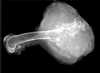

What is the arrow pointing to?

bone sequestrum

39